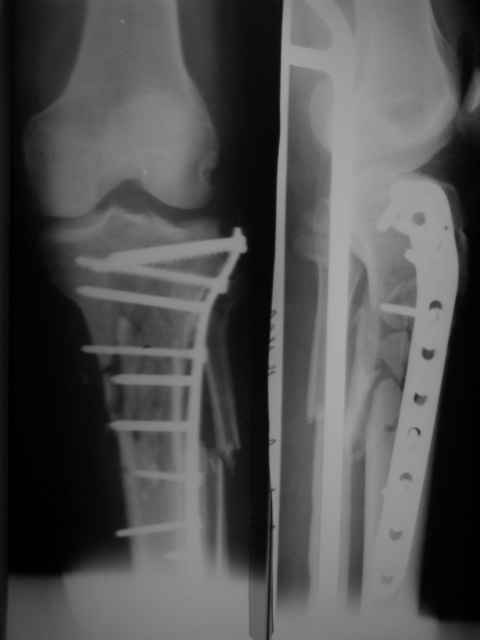

-Неудовлетворительная репозиция: вальгус, диастаз по медиальному кортикалу.

Вальгуса нет(мы не предоставили осевых снимков)

В диастазе стоит единственный отломок размером 1.2 на 2.5 по медиальной поверхности,остальные отломки всев контакте!

- Наверняка репозиция была открытой недели через две после травмы, а значит травматичной со скелетированием отломков.

Да

-В метаэпифиз необходимо было ввести минимум 3 блокированных винта на всю толщу спонгиозы.

Введено два блокируемых винта длинной 70 мм.и один спонгиозный.

-Какая (открытая или закрытая) была репозиция?

Репозиция была выполнена открыто(закрыто к сожалению не получилась-большие сроки и множество отломков)

-Чья это пластина?

LCP"SYNTHES"-прокимальная латеральная для б/берцовой кости